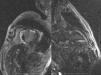

Late gadolinium enhancement (LGE) cardiac magnetic resonance imaging (MRI) is very useful in distinguishing between myocardial infarction, in which the enhancement is typically subendocardial, and myocarditis, in which it is subepicardial (Figure 1). In addition, various patterns have been described with different cardiomyopathies, in some cases enabling a specific diagnosis without invasive workup and risk stratification.1 Cardiac amyloidosis was previously thought to be present only when systemic amyloidosis was patently manifest. This has proved not to be the case, with cardiac MRI detecting increasing numbers of cases in patients with diastolic heart failure in whom cardiac involvement may be the first or sole manifestation. The pattern of LGE commonly found in cardiac amyloidosis is a global subendocardial enhancement with different contrast kinetics, the ventricular cavities showing no signal at all (Figures 2–6) compared to myocarditis and acute myocardial infarction, in which there is an intracavitary gray signal (Figure 1). Of 10 patients referred after echocardiography raised the suspicion of a cardiomyopathy, five were diagnosed with cardiac amyloidosis, two had images not suggestive of amyloidosis and were subsequently found to have Fabry's disease (Figure 7), and the other three probably had concentric left ventricular hypertrophy due to hypertension.